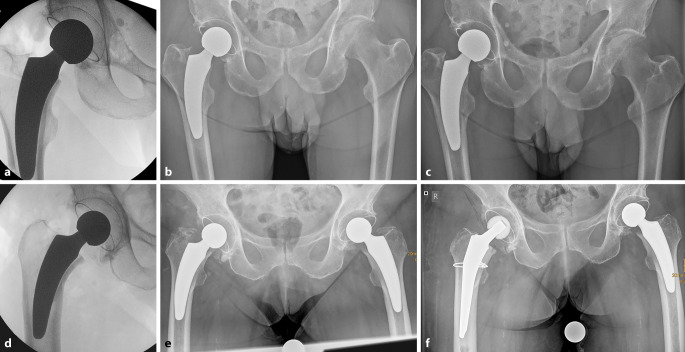

Short stems in total hip arthroplasty are increasingly being established and offer several advantages in terms of minimal invasiveness and bone preservation compared to standard implants. The rounded design and shorter stem length facilitate better adaptation to natural anatomy, at the same time also posing specific risks and complications. When transitioning to short stems, a learning curve must be considered. Careful patient selection and preoperative planning are crucial, and intraoperative imaging is recommended. The most common implant-specific complications include insufficient osseointegration, leading to subsidence and aseptic loosening, as well as periprosthetic fractures. The risk instability and dislocations as well as periprosthetic infections can potentially be reduced with short stems. This article discusses the frequency, causes, and treatment options for these types of complications and highlights current evidence-based treatment approaches.